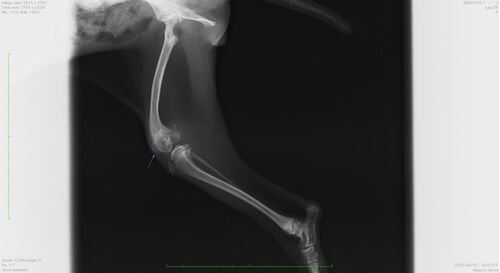

トイ・プードルの橈尺骨骨折に対するプレーティング

今回はトイ・プードルの橈尺骨骨折の手術のお話です。 8ヶ月の子で転倒してから左前肢の完全挙上で他院より紹介で来院されました。 レントゲン画像から橈骨・尺骨の2本とも骨折していることがわかります。 横から撮影したレントゲン画像 上から撮影したレ…